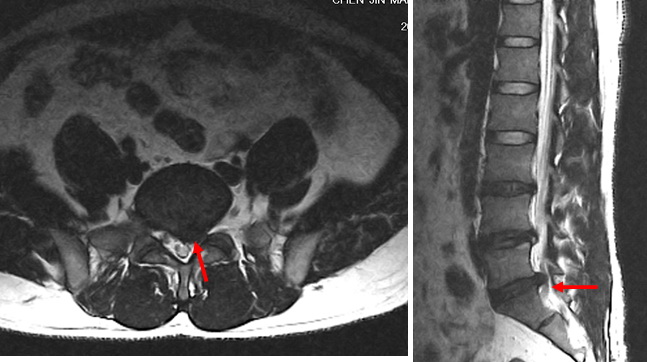

患者腰椎MRI显示L5-S1椎间盘突出明显,对左侧神经根明显压迫